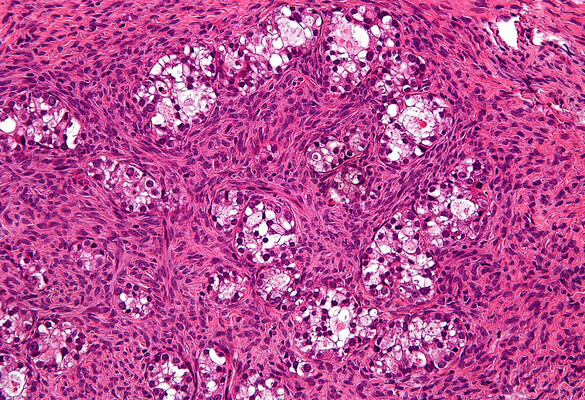

The compound candidates can reduce the tumor-forming ability of ovarian CSCs in mice (in contrast, paclitaxol may induce more ovarian CSCs at certain concentration).

mean ± SEM, n = 4 mice per group, **p < 0.01